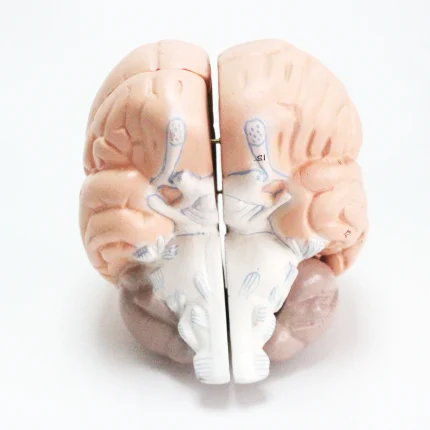

Modèle anatomique de cerveau humain

Modèle de cerveau humain

4 parties : (Fabriqué à partir de fibre de verre)

Modèle anatomique de cerveau humain

4 parties : (Fabriqué à partir de fibre de verre)

Ce cerveau est médialement divisé en deux parties, la moitié droite peut être démontée en frontal avec les lobes parentaux, le tronc cérébral avec les lobes temporaux et occipitaux en deux parties. Placé sur une base amovible avec Key Card numérotée.